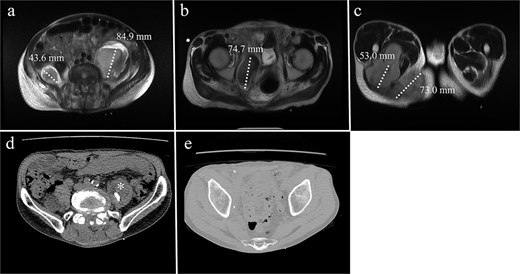

A 68-year-old male with a history of pelvic ring injury (fixation with two iliac screws 10 years prior) and degenerative lumbar spondylosis (spinal instrumentation 1 year prior) presented to the emergency department with fever and buttock pain. Magnetic resonance imaging revealed bilateral lobulated abscesses in the iliopsoas muscle (Fig. 5a–c). However, the abscess in the right psoas muscle extended caudally to the ischial tubercle and adductor muscles of the right thigh. Due to persistent fever with intractable pain in the right lower abdomen and right thigh, surgical debridement of the right psoas abscess was planned. The left psoas muscle was drained using a percutaneous CT-guided procedure because it was a solitary lesion.

MRI of a 68-year-old male with (a) bilateral psoas abscesses (right: 43.6 mm, left: 84.9 mm). The right abscess extended caudally to (b) the quadrilateral plate of the acetabulum and (c) the medial thigh and ischial tuberosity region. (d) Partial resolution of the right abscess with persistence of the left abscess (*). (e) Complete resolution of the right caudal extension after debridement.